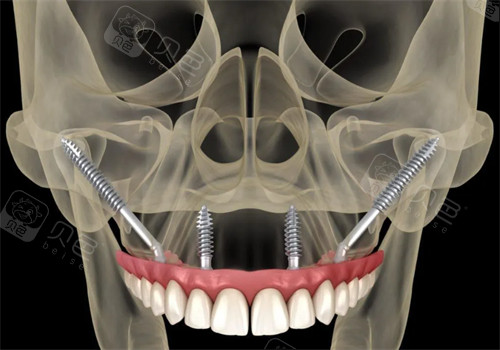

穿颧穿翼种植

穿颧穿翼技术动画示意图